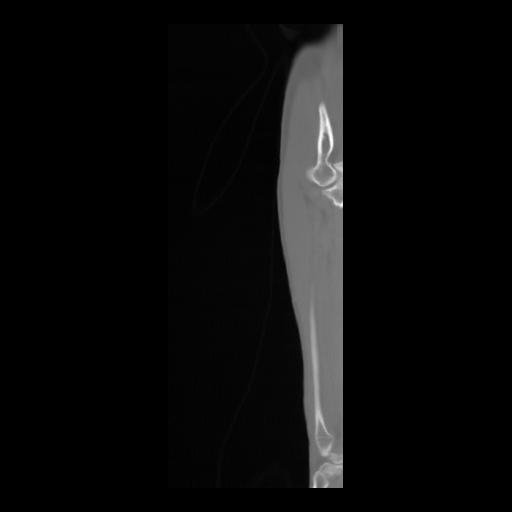

36 CUERPO,CE,Sagittal,3.000,CUERPO,Sagittal,